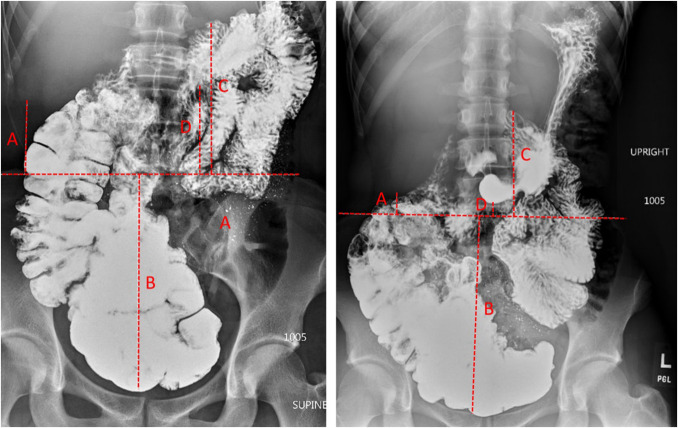

Methods: We systematically examined the prolapse of abdominal organs below their natural supine position (visceroptosis) during the upright small bowel barium study in healthy and hEDS subjects with irritable bowel syndrome.

Results: Comparison of age- and sex-matched healthy (n = 20) and hEDS (n = 10) subjects did not show any significant difference in dynamic movement of the viscera. Subgroup analysis did not demonstrate any correlation between the degree of prolapse, clinical symptoms, and hypermobility clinical (Beighton) scores. The interobserver reliability for 3 of the 4 anatomic landmarks showed "moderate" or "good" correlation based on their interclass correlation coefficients.